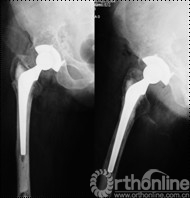

女,50岁,因髋关节发育不良继发骨关节炎行混合性固定(非骨水泥髋臼,骨水泥柄)THA手术。术后6年4个月发现腹股沟部渐增大、无痛性包块;体查:关节活动正常,腹股沟处可触及一10mm×10mm大小、质中等、移动度差、无触痛包块。超声检查提示右髂窝包块,呈强弱不等回声,大小约12cm×10cm,边界清楚。Harris评分88分。X线片示髋臼顶部DeLee和Charnley II区不规则低密度透光区,无连续骨小梁(图5)。CT片示髋臼假体上方DeLee和Charnley II区骨溶解区,DeLee和Charnley I、III区髋臼假体骨长入固定(图6)。WBC6.7×109/L,中性64%,ESR 28mm/h,CRP 8.34mg/L。聚乙烯线性磨损率为0.17mm/年,容积磨损率为543.42mm3/年,骨溶解区面积为412.52mm2。诊断:THA术后髋臼假体周围局灶性骨溶解(假体稳定)伴假性瘤样形成。

图5 翻修术前髋关节正侧位X线片示髋臼顶部DeLee和Charnley II区不规则低密度透光区(箭头所示),髋臼假体稳定固定

图9 髂腹股沟入路炎性假瘤切除、骨溶解病灶清除、同种异体颗粒骨植骨,髋关节后外侧入路更换高分子聚乙烯内衬为高交联聚乙烯内衬、更换股骨头术后

图10 术后2年随访,植骨替代吸收,髋臼骨溶解区新生骨组织替代,髋臼假体无移位、假体稳定固定